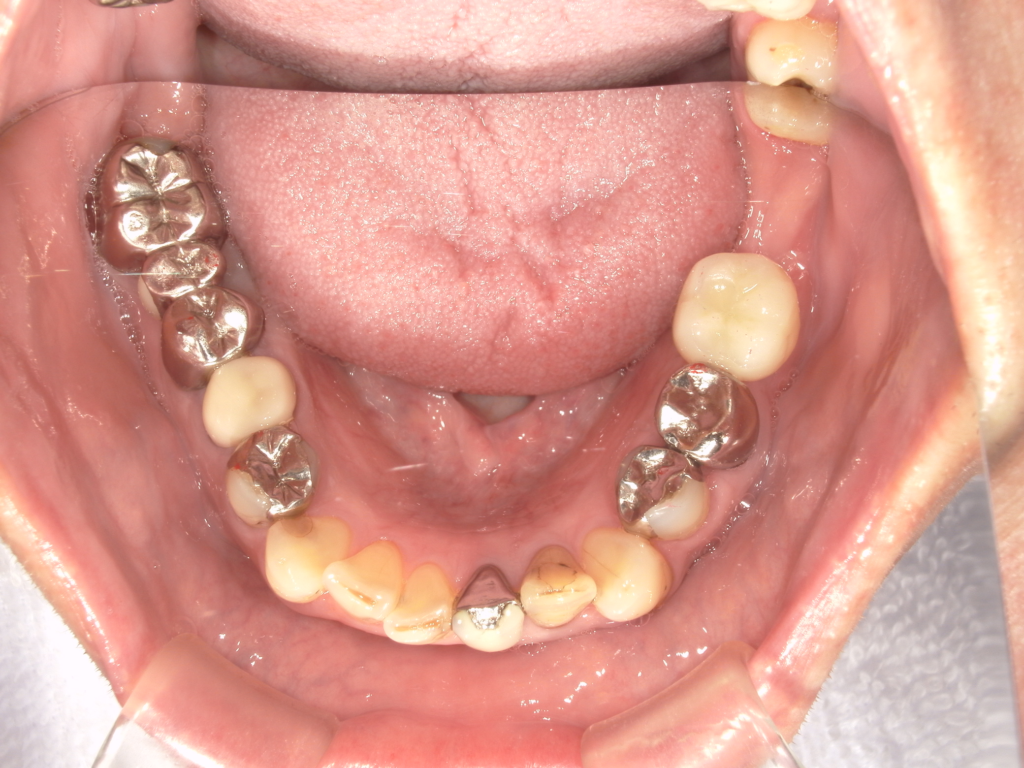

Y様インプラント実例 #44

左の上下の奥歯をインプラントで治療しています。

左下の奥歯は歯を抜くのと同時にインプラントの埋め込みを行っています。

被せものは上下、セラミックスで作っています。

治療前

治療後